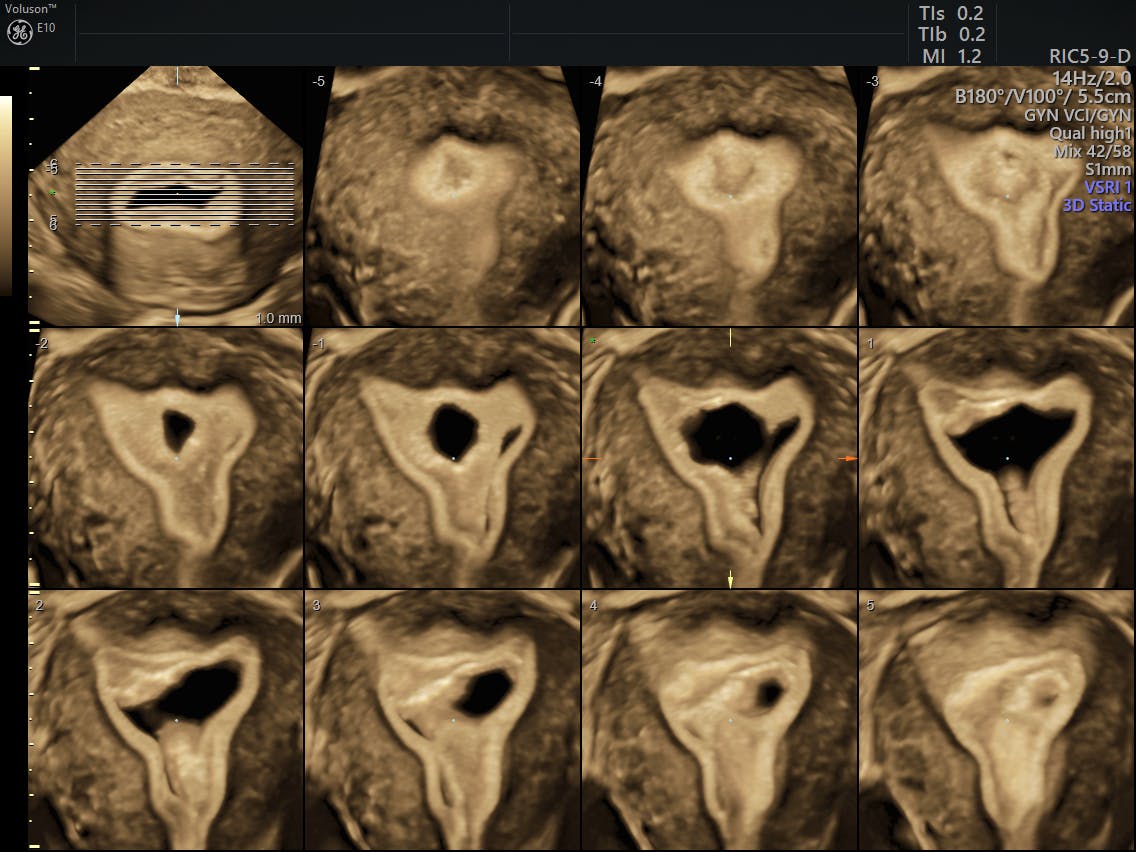

Three‐dimensional ultrasound imaging for discrimination between benign Postmenopausal Bleeding Ultrasound Scan postmenopausal bleeding always requires investigation and specialist referral to exclude genital tract disease. postmenopausal bleeding may be caused by the following: Because your final periods can be irregular, menopause is confirmed 12. menopause is the time after you have your last period. postmenopausal bleeding (pmb) refers to any vaginal bleeding that occurs in a menopausal woman. Postmenopausal Bleeding Ultrasound Scan.